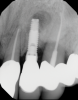

In this case, a dental implant that had been placed 10 years prior was functional, stable, and esthetically acceptable to the patient. However, a significant fistula was present on the facial-apical aspect of the ridge in the maxillary lateral incisor area. This area was painfully sensitive to touch and demonstrated purulence when squeezed. To evaluate the lesion, first, a conventional digital radiograph was acquired, which revealed an apical radiolucency at the apex of the implant (Figure 1). Further analysis using cone-beam computed tomography (CBCT) demonstrated a fistula from that site to the oral environment (Figure 2). Treatment options were discussed, including removal of the implant, followed by grafting, a healing period, and replacement of the implant and implant-retained crown. If this option was selected, a transitional appliance would need to be created. Another option was to attempt to salvage the implant and implant crown by treating the infection and grafting the site to create a new boney wall and eliminate the fistula. Ultimately, the patient accepted this option to attempt to salvage the fixture and crown.

(1.) Preoperative radiographic evaluation demonstrating a large radiolucency at the apical third of the body of an implant fixture replacing the patient’s maxillary left lateral incisor. The implant was stable, and the prosthesis was deemed esthetically acceptable by the patient.

Figure 1